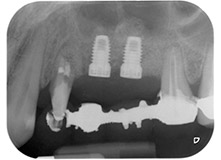

Mujer de 58 años de edad, que además es una apreciada colega y amiga, y se quejaba de dolor y de un aumento en la movilidad del pilar del puente de la pieza dental 24. También había inflamación periodontal, con bolsas de una profundidad de 7 mm en sentido mesiobucal y más de 12 mm en sentido distal, así como furcación de tercer grado. Asimismo, la radiografía reveló una lesión periodontal extensa alrededor de la región apical de la pieza dental 24 (figura 1) tratada previamente con endodoncia (alio loco).

En la raíz bucal, faltaba todo el hueso vestibular y distal. Básicamente, la fijación se limitó a la raíz palatal, lo que corroboró el mal pronóstico preliminar. La pieza 27 también mostró una fijación horizontal reducida (figura 12) y una rarefacción apical mínima (figura 1), si bien sin síntomas clínicos.